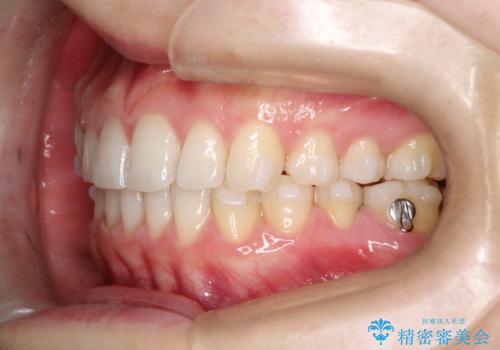

治療前は臼歯部反対咬合のため下顎が偏移し正中がずれていましたが、臼歯部反対咬合を改善したことで、正中のズレを改善することができました。